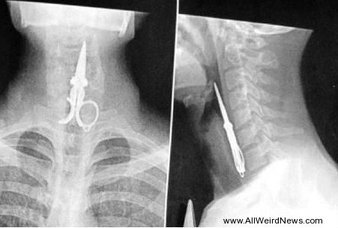

8②のハサミって医療ミスかよ。

リアルに本間先生みたいなミスする先生いるんだ…

ガーゼの体内置き忘れは年に一度か二度くらいニュースで見るから、こういうのって発覚してないもの含めたら結構多いんじゃない?

にしたって刃物は怖いよね